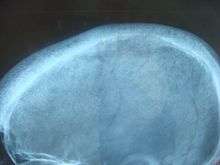

Pepper & Salt, classical X-Ray appearance of hyperparathyroidisim